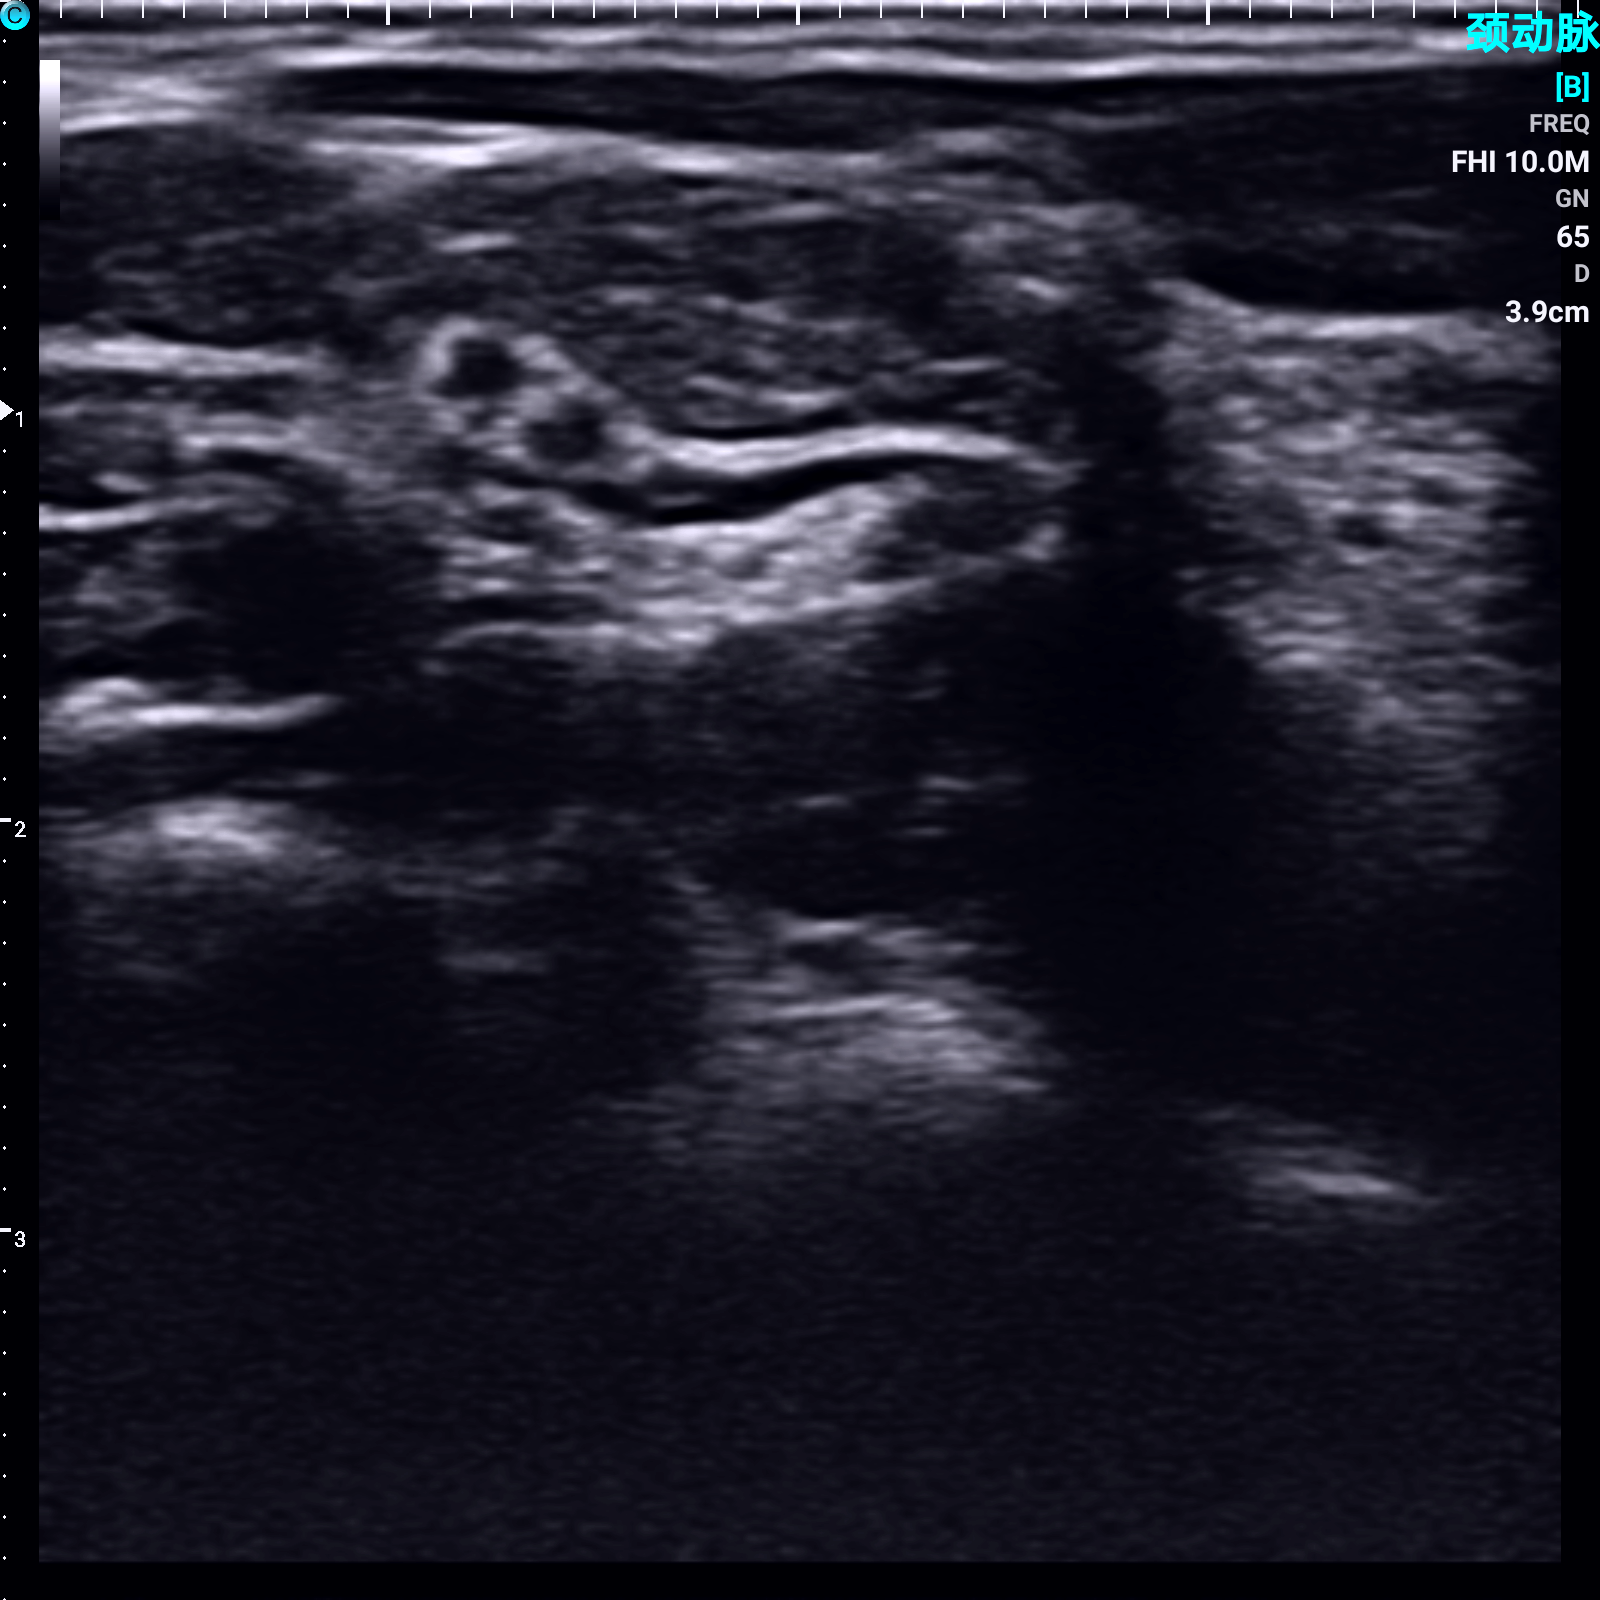

尺神经 B模式

颈动脉 PW模式